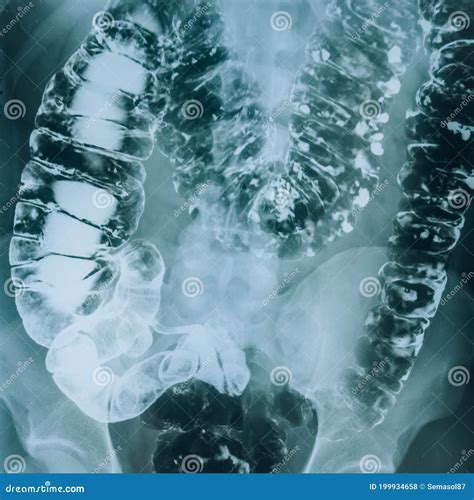

The large intestine, also known as the colon, is shorter but wider than the small intestine. It is divided into several sections: the cecum, ascending colon, transverse colon, descending colon, and sigmoid colon. The large intestine plays a crucial role in absorbing water and electrolytes from the remaining indigestible food matter, forming stool in the process. Additionally, it houses beneficial bacteria that aid in digestion and immune function.